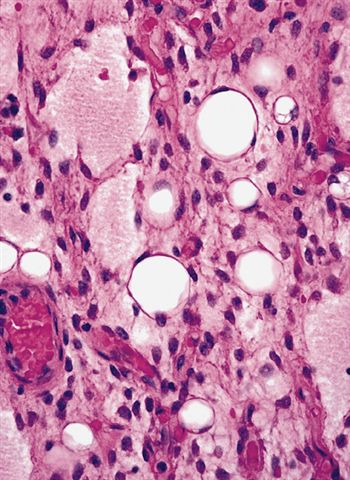

- Low grade

- Paucicellular with monomorphic, stellate or fusiform shaped cells without atypia; striking in their blandness, so much so that any significant pleomorphism should cause one to pause

- Prominent plexiform vasculature (delicate thin walled arborizing and curving capillaries that form a network reminiscent of chicken wire fencing)

- Numerous signet ring lipoblasts, particularly at periphery of lobules

- Mucoid matrix is rich in hyaluronic acid that may form large mucoid pools (so called pulmonary edema pattern)

- Will be positive for stromal mucin stains such as Alcian blue (see Microscopic (histologic) images)

- High grade

- Hypercellular solid sheets of back to back cells with round cell or primitive cytomorphology in > 5% of the sampled tumor

- Cells can have a small amount of hypereosinophilic cytoplasm, a finding of no clinical significance but of significant diagnostic confusion, especially in a limited sample